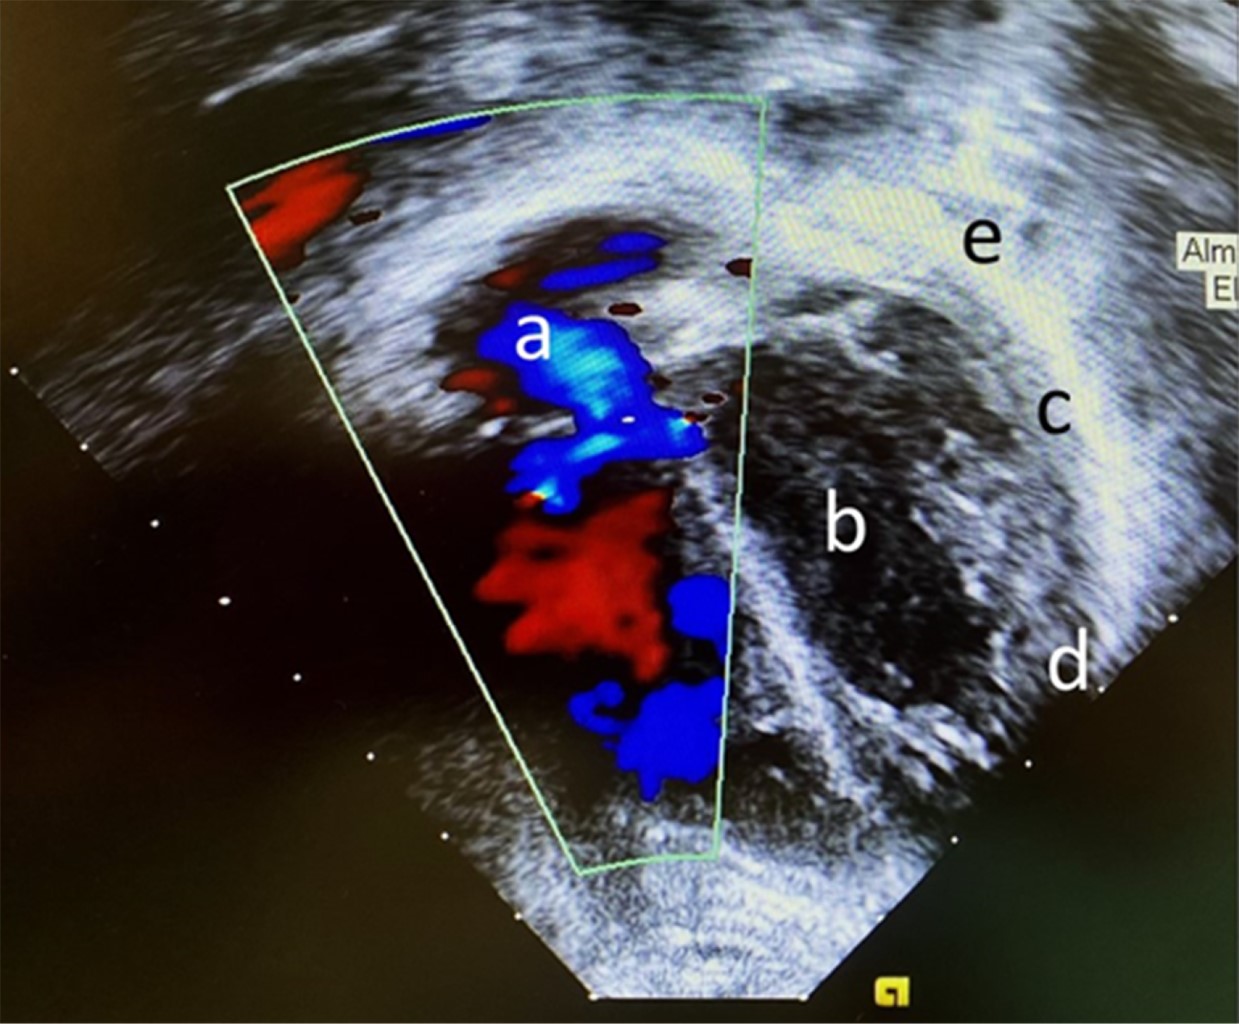

Radiografía de tórax con presencia de infiltrado grueso diseminado (Figura 1).

Retiro de la ventilación mecánica a las 24 horas, se dejó manejo de sostén; sin embargo, ante la persistencia durante 72 horas de taquicardia (180-210 lpm), además de presiones arteriales que oscilaron entre 90/62-108/71 mmHg, se sospechó afectación cardiaca, por lo que se realizó ecocardiograma, el cual reportó: derrame pericárdico leve, pericardio hiperecogénico, engrosado, sin datos de restricción, hipertensión pulmonar leve (35 mmHg), disquinesia generalizada y dilatación leve de cavidades (Figura 2).

Figura 1